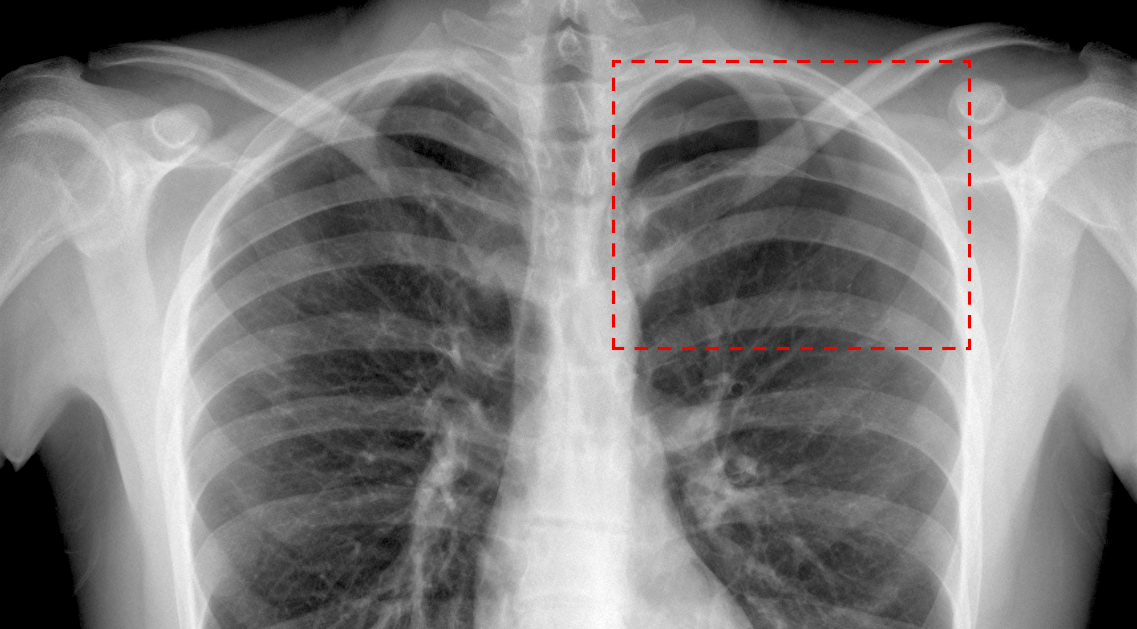

Et la société Milvue en fait partie. Créée en 2018, elle développe et commercialise une solution d’intelligence artificielle (IA) pour la radiographie des urgences. Elle sert à prioriser les radiographies d’urgence pour aider à la détection d’anomalies thoraciques ou en traumatologie. « En métropole, quatre radiographies d’urgence sur cinq ne sont pas directement interprétées par un radiologue, mais en différé avec une moyenne de 12 à 72h de délai », explique Alexandre Parpaleix, président et co-fondateur de Milvue et médecin radiologue à l’hôpital Saint-Antoine à Paris.

Déployée dans une dizaine de centres de radiologie et hôpitaux, pour l’instant, Milvue traite entre 250 et 300 examens par jour en métropole. La solution est vendue sous forme d’abonnement annuel selon les volumes traités par les hôpitaux. « Rapporté au prix d’un examen, l’abonnement vaut à peu de choses près 1 euros 50 la radiographie [soit un peu moins de 180 francs CFP, ndlr] pour l’hôpital », précise Alexandre Parpaleix. « Si nous avons un logiciel qui met en évidence les 30% d’examens pathologiques, nous maximisons le temps et la concentration des professionnels de santé sur ces examens ».

L’idée est donc d’avoir un logiciel qui a appris, sur des centaines de milliers de cas, à différencier les symptômes. Cet algorithme va tourner sur chaque image produite aux urgences et permettre au médecin d’avoir une « vision sécurisée » de son interprétation. Avec l’émergence de l’IA, la radiologie apparaît comme la spécialité la plus menacée, remplaçant complètement le radiologue. Ce futur reste bien éloigné de la vérité, selon le co-fondateur de Milvue. « Cela va permettre de le remettre dans le jeu de l’expertise de diagnostic. Nous redonnons la main au radiologue ».